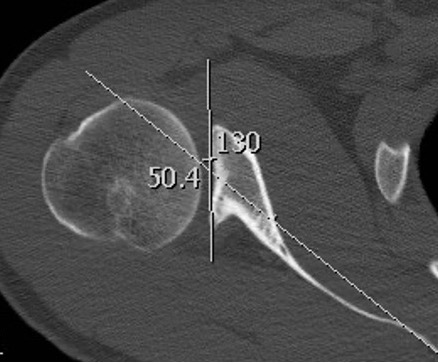

Reverse Hill Sachs / Posterior bony Bankart / Glenoid retroversion

CT

Hill Sachs lesion / posterior bony bankart / glenoid retroversion

Glenoid Osteotomy

Indication

Posterior instability with retroversion > 10 degrees / glenoid dysplasia